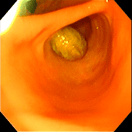

‣当院での症例紹介

異物:1円玉

異物:裁縫針

異物:梅干しの種

胃腺癌

胃瘻チューブ設置

炎症性ポリープ

炎症性ポリープ⑵

気管虚脱

気管支腫瘍

気管腫瘍

喉頭腫瘍

食道内異物回収後

鼻腔内腫瘍(犬)

鼻腔内腫瘍(猫)

慢性腸症(犬)

慢性腸症(猫)